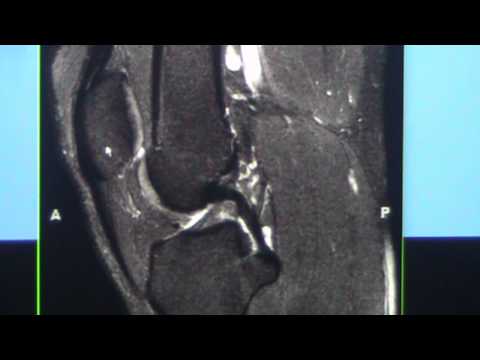

Meniscal Tears

Radiology Rounds: MRI of the Knee Part 1 - Dr. Avneesh Chhabra

This educational presentation reviews the knee MRI and is directed at orthopaedic and radiology residents.